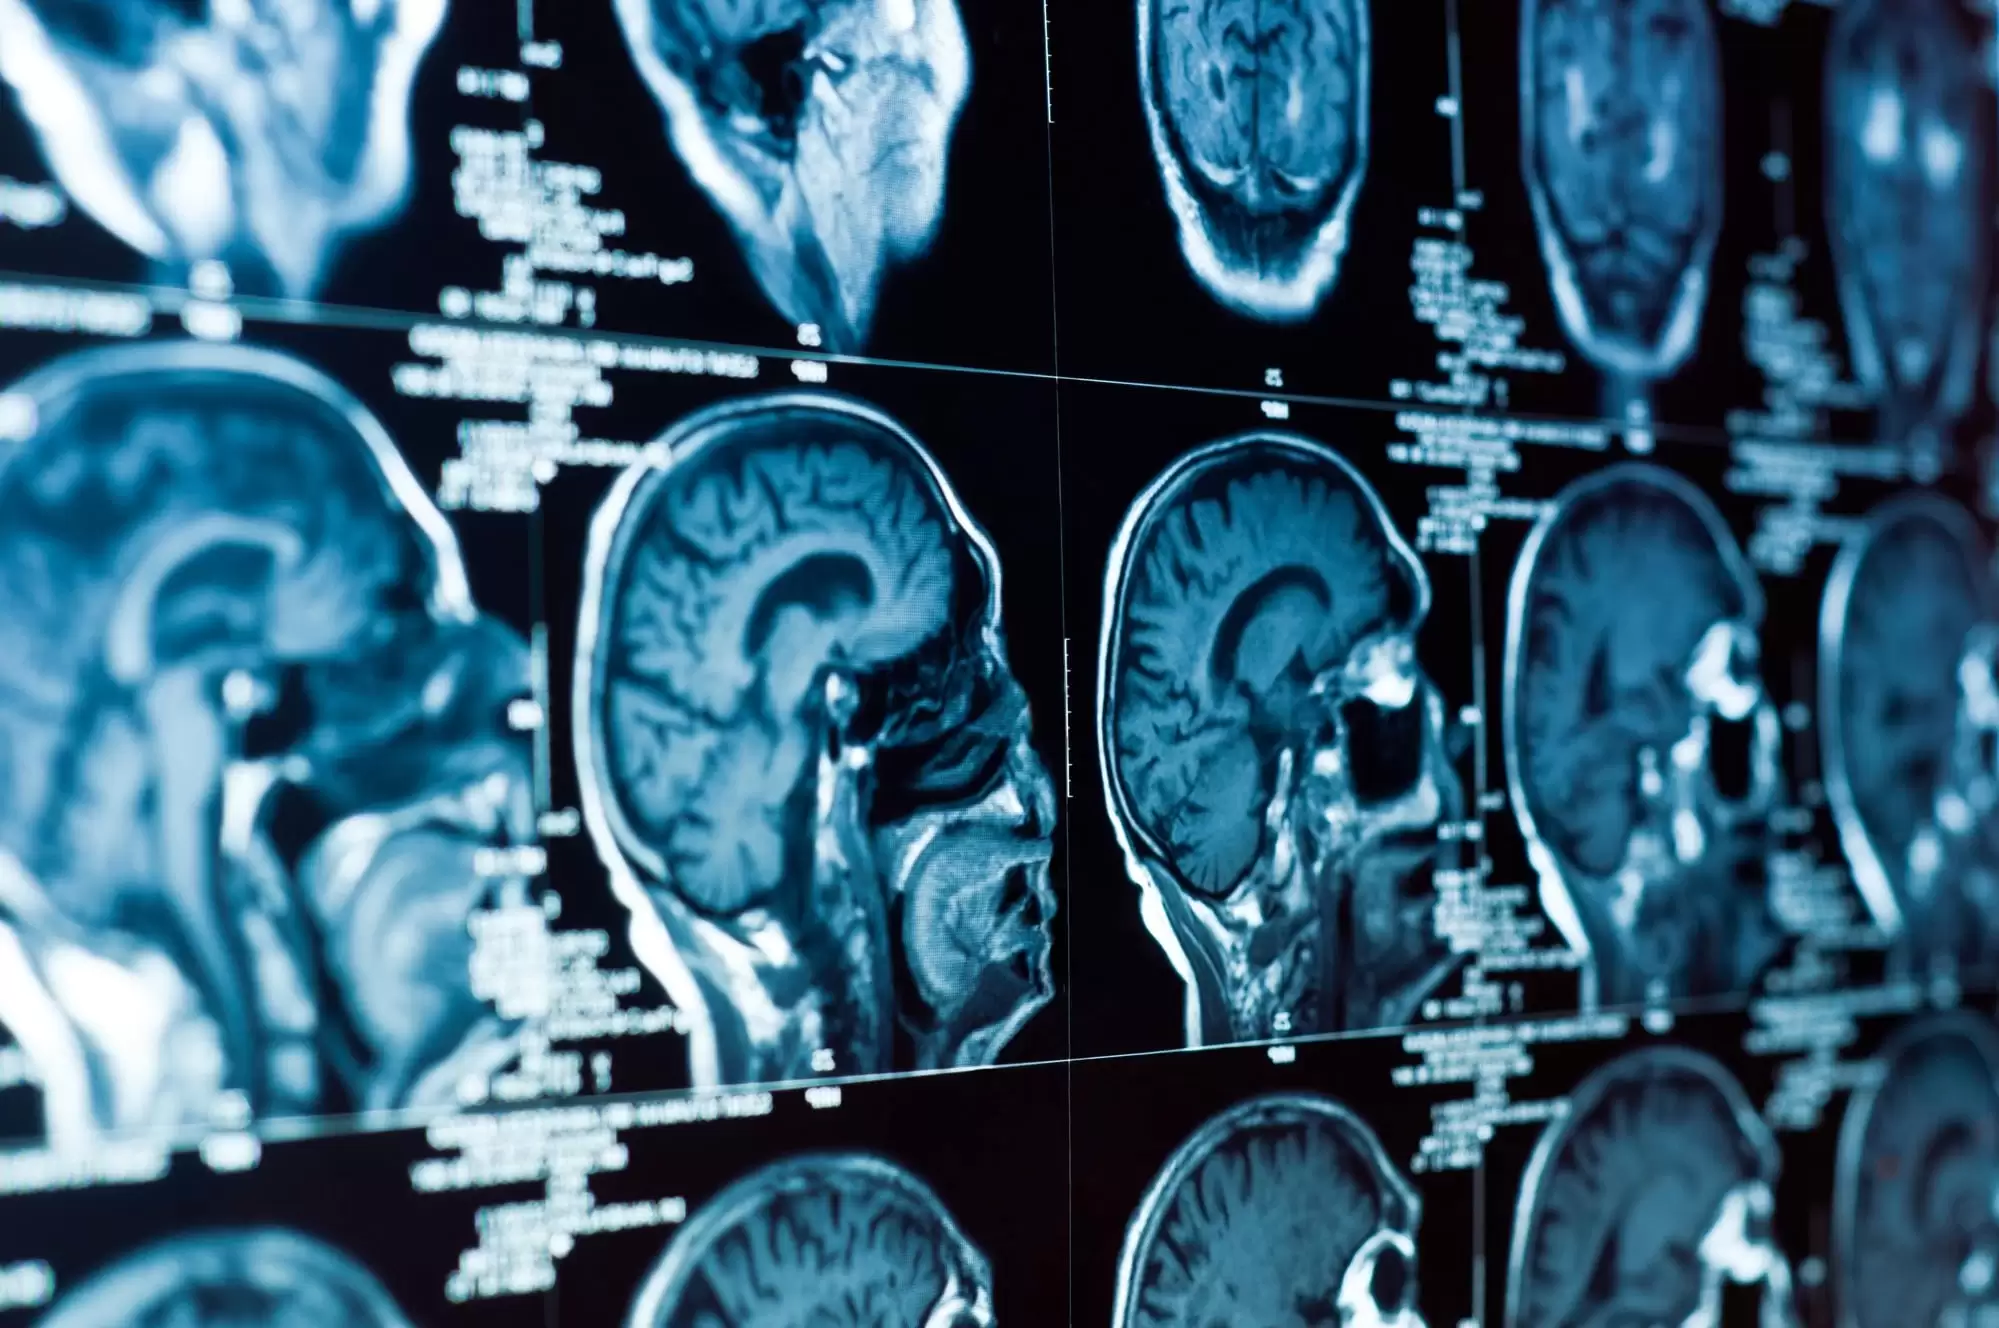

Establishing the full extent of a brain injury requires comprehensive medical documentation and often testimony from specialists. Key evidence includes emergency room records and imaging studies, neurological evaluations, neuropsychological testing results, treatment records from rehabilitation therapists, testimony from treating physicians, statements from family members about observed changes, and documentation of work limitations and lost income.